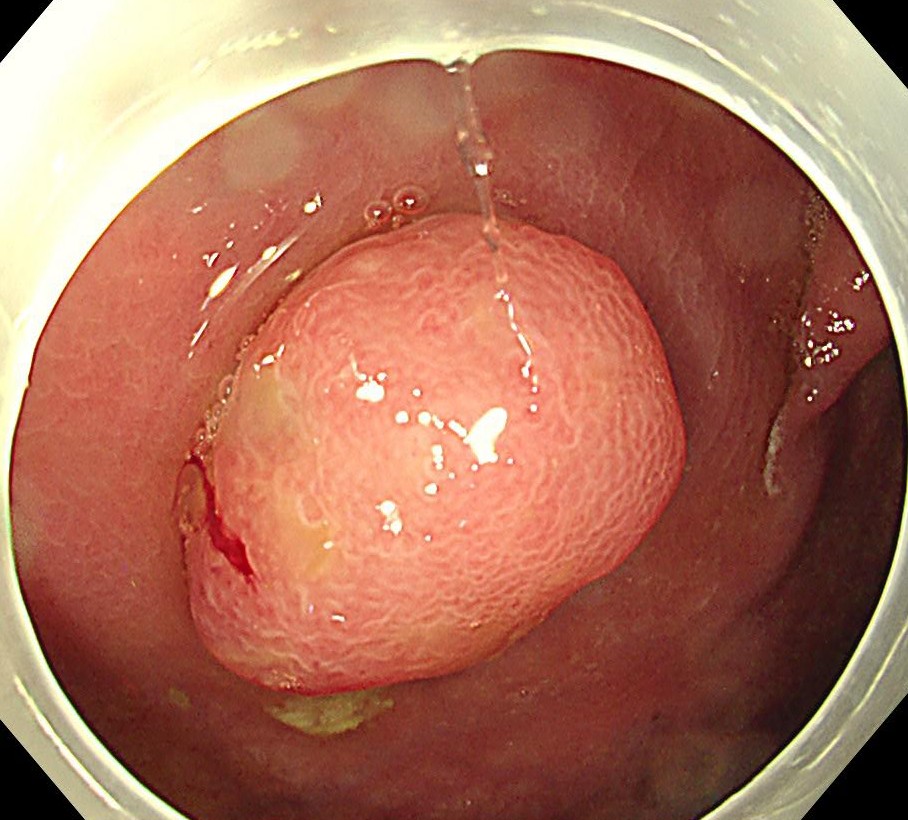

中年女性、下血にて来院。大腸内視鏡をしますと、直腸に15mm大のポリープを認めます。NBI(狭帯域光観察)では構造異形は乏しく、良性ポリープと診断しましたが、下血原因と考え、型のごとく内視鏡切除(EMR)しました。

病理診断にて直腸のSSA/P (sessile serrated adenoma/polyp 鋸歯状腺腫) と診断されました。大腸の鋸歯状腺腫はよくみられる病変ですが、右側結腸に多く、直腸は過形成性ポリープがほとんどで、直腸SSL (鋸歯状病変)は比較的まれです。またその多くが平坦な病変であるため、上記のようなⅠ型のポリープ形状は珍しい病変と思われます。最近の研究結果で直腸の隆起型のSSA/Pはがん化率が高いとする報告も散見され、注意を要する病変と思われます。